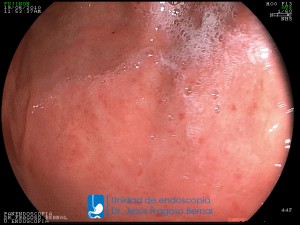

La Unidad de Endoscopía fue creada en 2002 por el Dr. Jesús Fragoso Bernal, es pionera en el estado por la utilización de la tecnología más avanzada, que nos permite ofrecer servicios integrales de diagnóstico y tratamiento para las enfermedades del aparato digestivo.